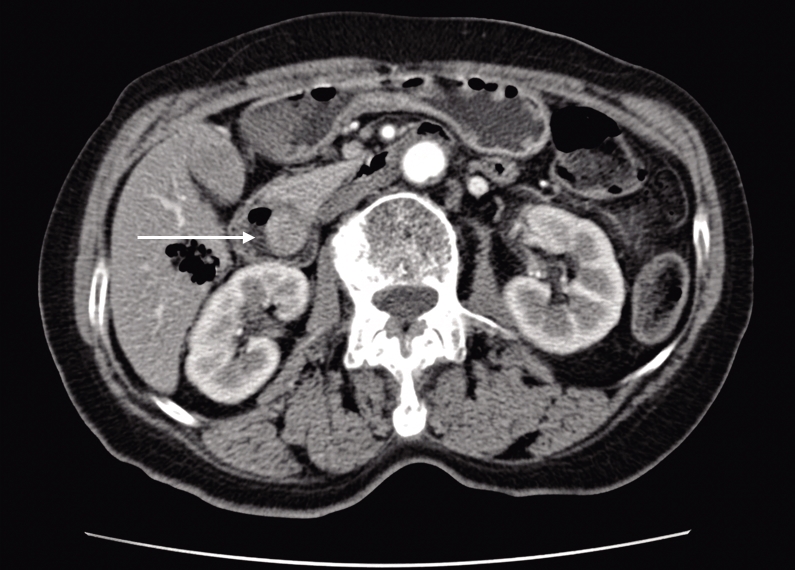

图1 十二指肠壶腹区富血供肿物,呈明显较均匀强化(箭头所示)Fig.1